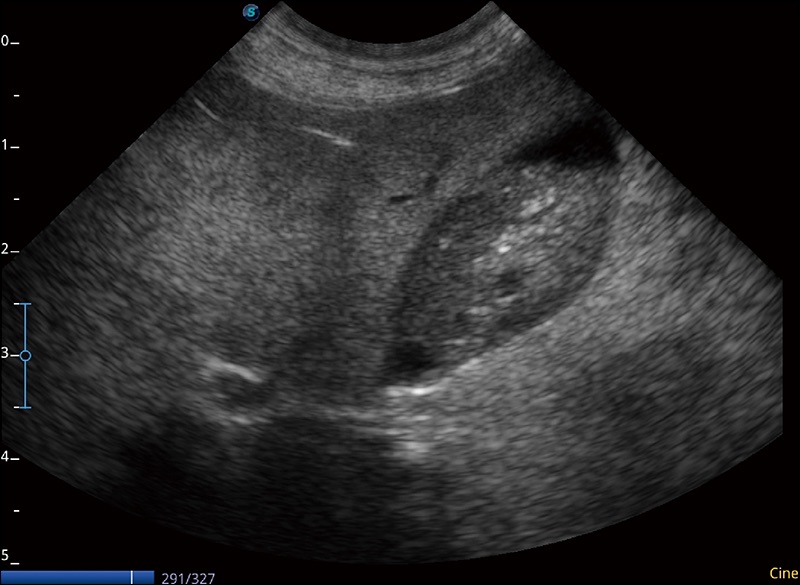

α1卓越的图像质量和便捷的工作流程,使每位宠物医生都能轻松扫查。其全面的兽用应用功能和紧凑型的结构设计,可以满足动物检查的多种需要。专业的预设检查模式和多领域测量软件包有助于为不同类型的动物提供检查, 让宠物医生能够出色的完成工作。

任意波束合成技术

在不牺牲时间分辨率的情况下提供出色的图像

空间复合成像

优化不同角度的图像

实时宽景成像

可实时观察感兴趣区域和病变位置